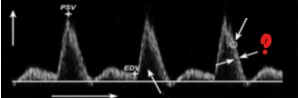

What represents the question mark on this image?

Spectral window